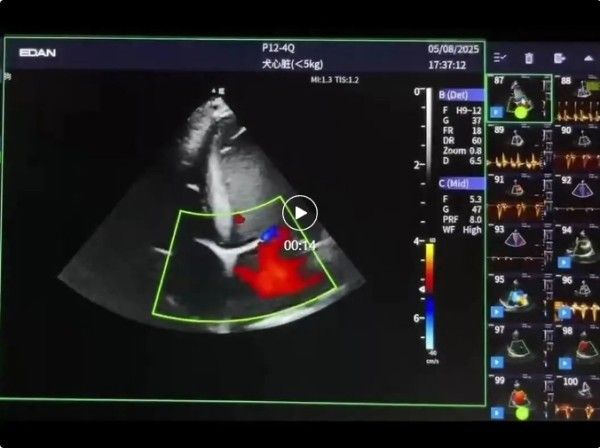

收官之日聚焦左心切面扫查、彩色多普勒技术及报告撰写,陈立坤老师系统传授左侧胸骨旁心尖四腔、两腔切面等左心系列切面获取技巧,并结合彩色多普勒超声心动图的临床运用,解析血流形态、压差评估及异常识别方法。

实操环节涵盖左心切面扫查演示、彩色多普勒操作及心超报告撰写考核,确保学员能够独立完成标准化心超检查报告。